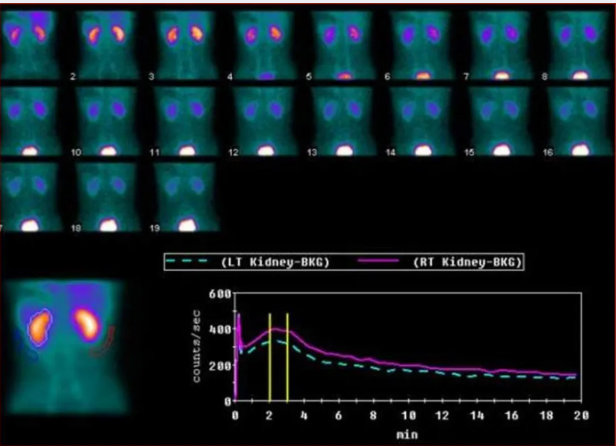

肾动态显像

判断肾实质功能、评价分肾实质功能(GFR的测定)、移植肾的监测、上尿路梗阻的诊断与鉴别诊断、诊断肾血管性高血压等。

▲肾动态显像及GFR的测定